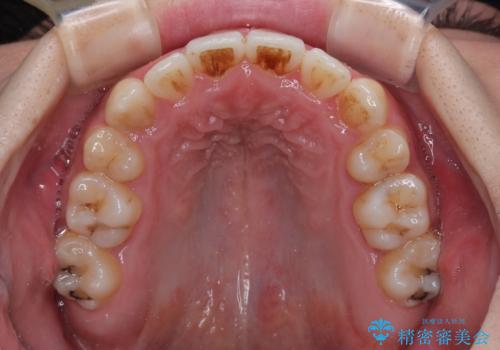

上下の八重歯とクロスバイト ワイヤー装置での抜歯矯正

前歯の歯列が整ったことで、歯磨きが大変やりやすくなり、患者様には大変満足していただけました。